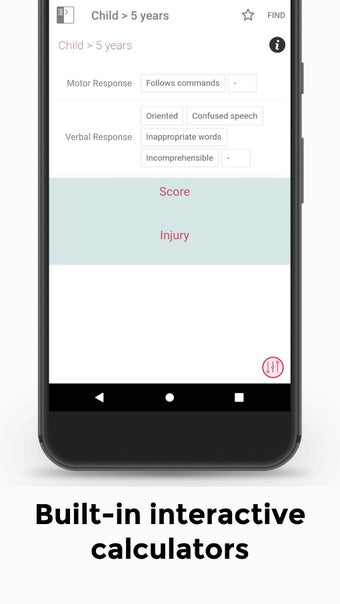

この無料アプリには、日常の実践に役立つ多くの情報が含まれています。このアプリでカバーされるトピックは、疾患から薬剤、さまざまなタイプの傷害まで幅広く、患者ケアを担当する人々にとって素晴らしいリソースです。